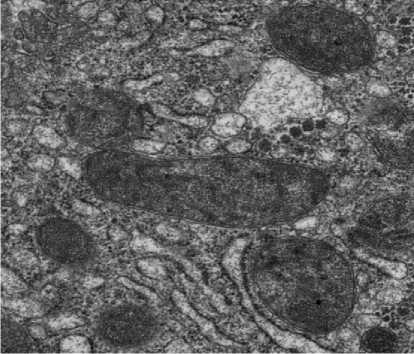

Ультратонкие срезы толщиной 70–90 нм изготавливались на ультрамикротоме, контрастировались уранилацетатом и цитратом свинца по Рейнольдсу. Исследование проводилось на трансмиссионном электронном микроскопе HITACHI HT7800 (Hitachi High-Tech Corporation, Япония) при ускоряющем напряжении 80 кВ. Цифровые изображения получали с помощью встроенной CCD-камеры.

Оценивались следующие ультраструктурные параметры: состояние митохондрий (набухание, деструкция крист, электронная плотность матрикса), целостность мембран эндоплазматического ретикулума, состояние ядерной оболочки и распределение хроматина, сохранность межклеточных контактов (десмосомы, плотные контакты), наличие аутофагосом и признаков апоптоза, состояние синусоидального эндотелия и пространств Диссе. Полуко-личественная оценка ультраструктурных повреждений проводилась по 4-балльной шкале (0 — норма, 1 — минимальные изменения, 2 — умеренные изменения, 3 — выраженные изменения) в не менее чем 20 клетках на образец.

Д

Рисунок 2. Гистологические признаки ишемически-реперфузионного повреждения трансплантатов печени в группах сравнения. А. Группа HOPE, ТЭМ — митохондрии с сохранной двухконтурной мембраной, дифференцируемыми кристами, точка Т4. Б. Митохондрии с нарушением целостности мембраны, разрушением крист. Группа холодового статического хранения. ТЭМ, точка Т4. В. Группа HOPE, точка Т2. Вакуолизация цитоплазмы гепатоцитов, кариопикноз ядер. Окраска толуидиновым синим, ×400. Г. Митохондрии неправильной формы с деформированными и разрушенными кристами. Группа холодового статического хранения. ТЭМ, точка Т2. Д. Некроз гепатоцитов в 1 зоне ацинуса. Окраска толуидиновым синим, ×400. Группа холодового статического хранения. Точка Т2 Figure 2. Histological features of ischemia-reperfusion injury in liver grafts across comparison groups. A. HOPE group, TEM — mitochondria with intact double-membrane, differentiable cristae, time point T4. Б. Mitochondria with disrupted membrane integrity and cristae destruction. Cold static storage group. TEM, time point T4. В. HOPE group, time point T2. Vacuolization of hepatocyte cytoplasm, karyopyknosis of nuclei. Toluidine blue staining, ×400. Г. Irregularly shaped mitochondria with deformed and destroyed cristae. Cold static storage group. TEM, time point T2. Д. Hepatocyte necrosis in acinar zone 1. Toluidine blue staining, ×400. Cold static storage group. Time point T2